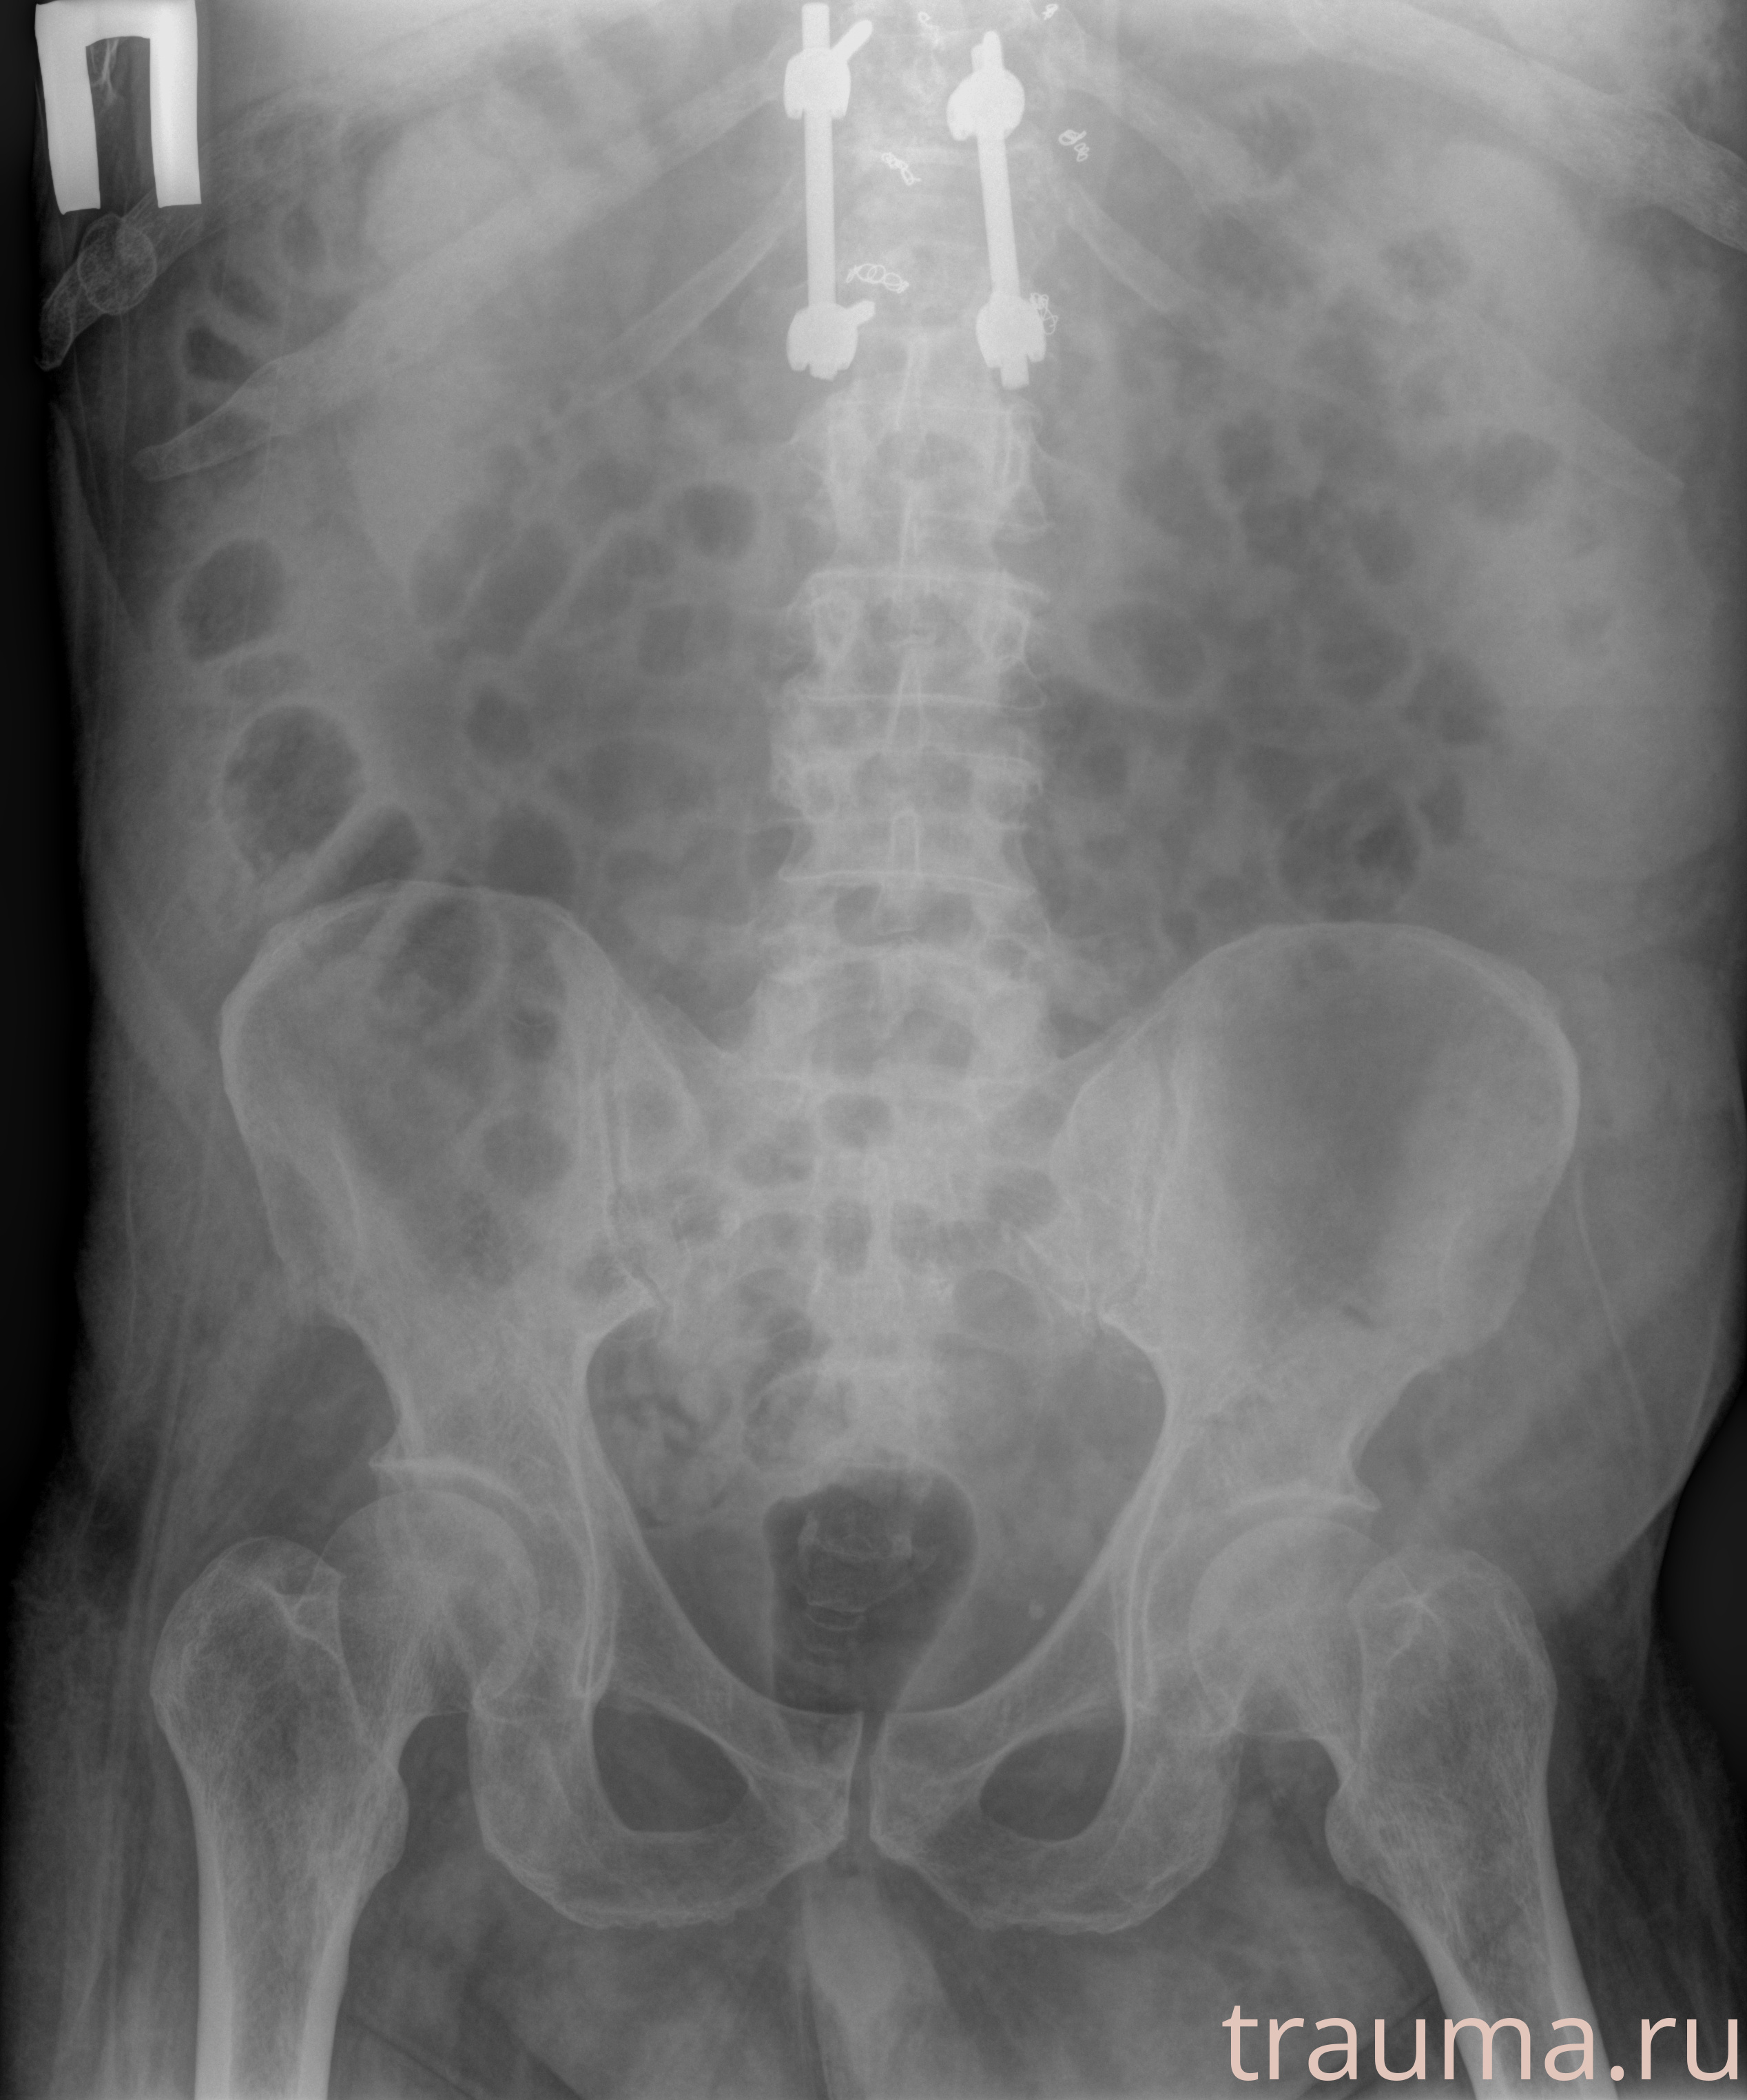

Рентгенограммы

Рентген на дому: по вашему адресу приезжает врач-рентгенолог, травматолог-ортопед с мобильным рентгеновским аппаратом, проводит диагностику травмы или заболевания, делает необходимые рентгенограммы, дает рекомендации по дальнейшему лечению. Получить качественные снимки в домашних условиях возможно благодаря уникальной методике, разработанной МосРентген Центром для института  Склифосовского